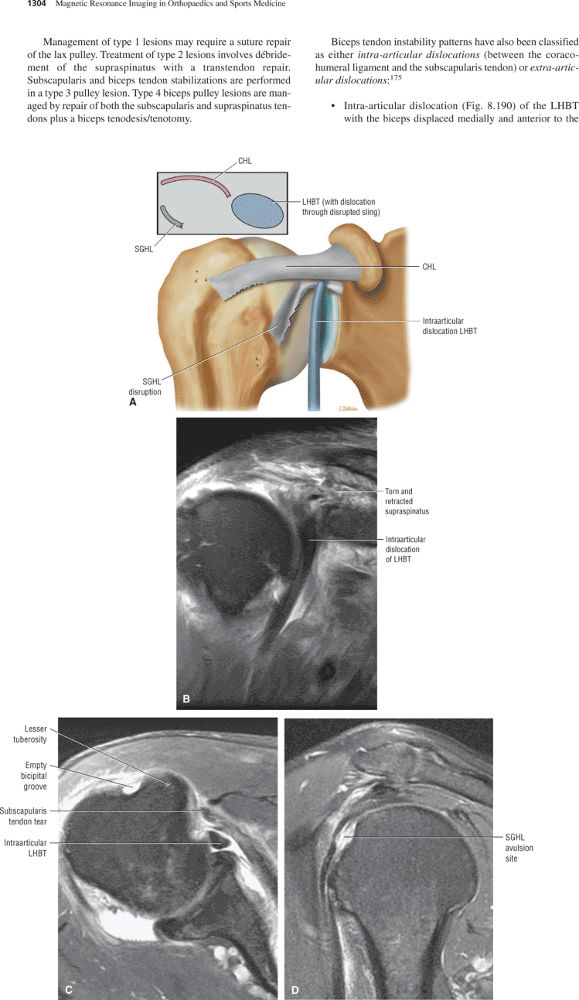

of the humeral head. Warner et al. showed that the SGHL was well developed in 50% of shoulders.69 When present and well formed (developed), the SGHL represents the primary capsuloligamentous restraint to inferior translation of the unloaded, abducted shoulder joint.59,69 Both the SGHL and the CHL have an important role in forming the biceps pulley of the rotator cuff interval.

The rotator cuff interval is located between the superior aspect of the subscapularis tendon and the inferior aspect of the supraspinatus tendon. This interval contains the coracohumeral ligament and the SGHL. A hidden lesion of the rotator interval has been attributed to pathology of the CHL–SGHL confluence, which forms the biceps sling or pulley. Surgical closure of the interval appears to eliminate excessive inferior translation.59